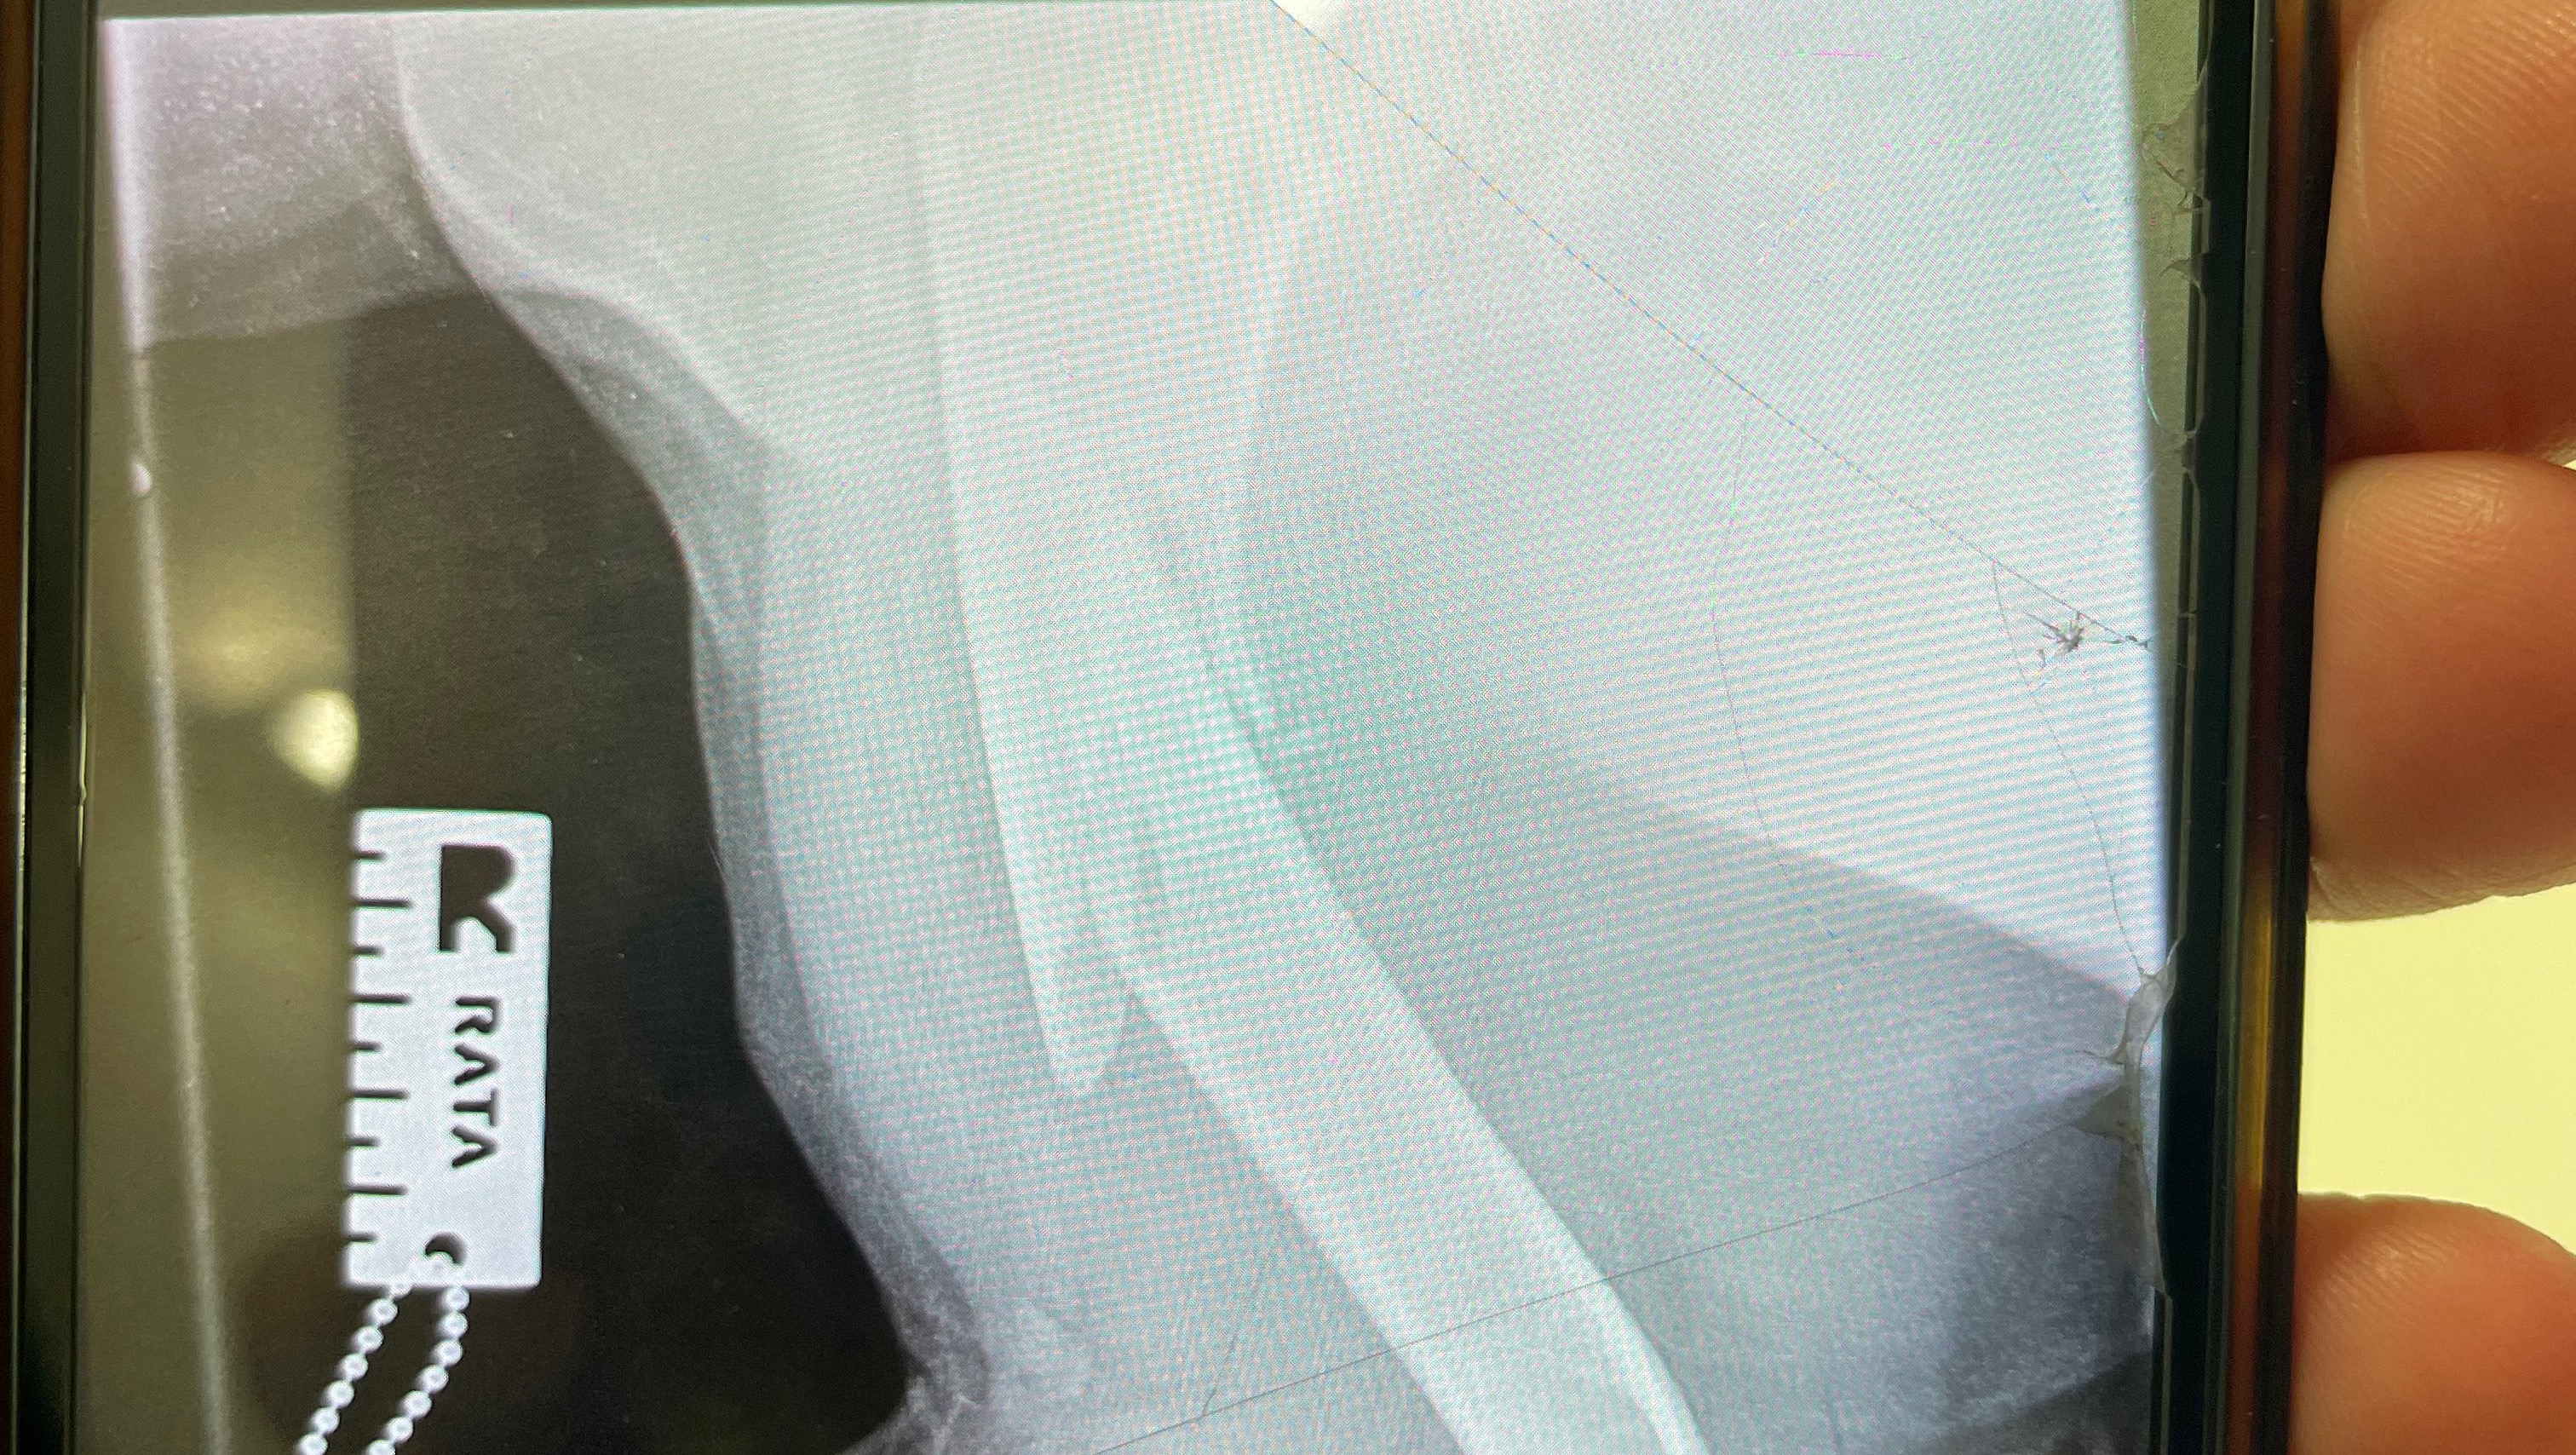

After rushing Bishop to the vets after his slip, X-rays revealed the extent of the break and resulting in him having to be admitted to the emergency vet hospital to mange his pain and prepare him for surgery and his post recovery. The surgery will involve a bone biopsy to ensure there is no underlying lying cause for such a large break and plates and a bone marrow graft to help with the healing. He will then need up to 3 nights post op stay and care at the vet hospital to recover before he can come home.